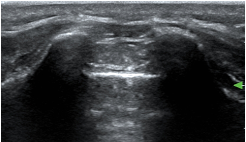

- Identify targets (nerves, fascial planes) – example 1, median nerve to the forearm

- Identify nearby structures (blood vessels, bowel, bone, pleura) which allows you to avoid complications (especially in small children where target structures and nearby structures are in immediate proximity or very superficial) – example 2, supraclavicular plexus in neonate: very little space between plexus, vessels, pleura, ribs.

- At birth, the ossification centres of the spine are at an early stage of development; it is therefore possible to obtain excellent spinal images in neonates. With age and increasing ossification, the US window to the spine diminishes (the ossification is complete at 21 years old)

Caudal in a neonate

Caudal in a two year old